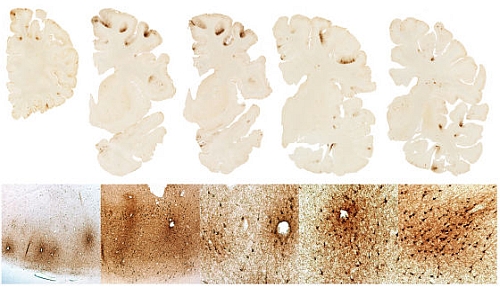

アメフト選手は慢性外傷性脳症になる

2017年4月に刑務所内で自殺した元アメリカンフットボール選手の脳を解剖したら

慢性外傷性脳症を患っていたと判明したそうです。Aaron Hernandez suffered from most severe CTE ever found in a person his age

彼は恋人を殺害した容疑で刑務所に収監されていました。

しかし2017年4月に刑務所内で自殺したとのこと。要はボクシングのパンチドランカーみたいなものですね。

行動や意思決定をする前頭葉が損傷していたとのこと。

慢性外傷性脳症は死語に脳を解剖しないとわからない障害のようです。

生前から慢性外傷性脳症だったとはわからなかったのですね。 -